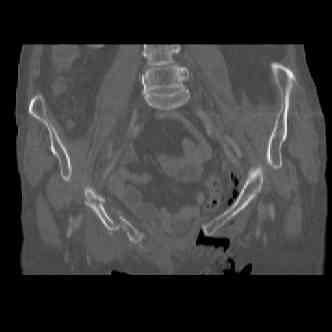

attached are several CT cuts. please let me know if you need more. the CT is pre-pelvic ex-fix placement.

I wouldn't plate the front.

But I would add screws posteriorly.